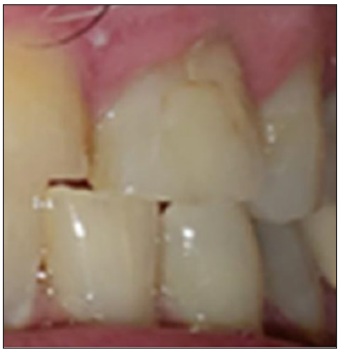

Radiograph and intraoral examinations reveal worn-down teeth [#s 07, 08 and 09] (Figures 1-5) as well as tooth gemination [# 10] (Figures 1-7). The evaluation of periapical radiographs taken of teeth [#s 07, 08, 09, and 10] presents with no evidence of periapical radiolucency. Tooth [# 08], however, shows significant internal root resorption to the mid-way and calcified the apical half of the root to the apex. Tooth [# 09] also shows a significant external/internal root resorption which is more evident on the distal aspect of the tooth, (Figure 7). Both merged segments of geminated tooth [#10] (Figure 6), shows almost completely calcified root canals to the apex. This calcification is also evident in tooth [# 07] (Figure 7).

Figure 3: Maxillary occlusal view heavy attrition on incisal edges of anterior teeth oversized/abnormally shaped of geminated tooth # 10.

Figure 4: Facial / Labial view oversized/abnormally shaped geminated tooth # 10.